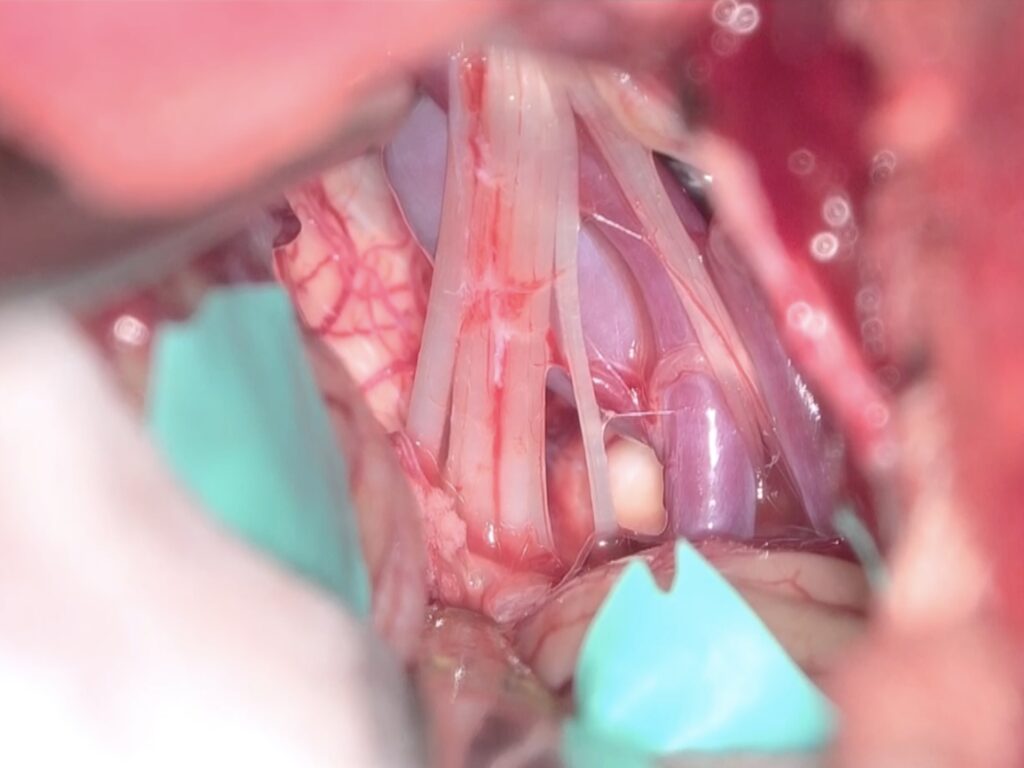

2603月 67歳男性の右顔面痙攣を手術しました。 2026 4/20 顔面痙攣・三叉神経痛 2026年3月22日2026年4月20日この患者さんもVA圧迫型でしたが、延髄誘発電位のM-TEPを併用しABR、ICGなど術中画像支援を駆使して手術を行いました。合併症なくうまく治癒できました。ScreenshotScreenshotScreenshotScreenshotScreenshotScreenshotScreenshotScreenshotScreenshotScreenshotScreenshotScreenshotScreenshotScreenshot 顔面痙攣・三叉神経痛 よかったらシェアしてね! URLをコピーしました! URLをコピーしました! 260306金 北海道神経セミナーで講演しました。 260313金 STROKE2026 1日目 この記事を書いた人 kikuta 関連記事 2603月 58歳女性の左顔面痙攣を治療しました。VAとAICAの複合型圧迫でしたがうまく治癒できました。 2026年3月21日 46歳男性、開眼できないほどのVA型左顔面痙攣を手術しました。術後まだ完全には消失していませんが痙攣は著明に軽減しました。 2026年3月3日 19歳女性の三叉神経痛を手術しました。術後痛みは消失した様子です。 2026年3月3日 87歳女性、繰り返しブロックを行いガンマナイフも行った、難治生三叉神経痛を手術しました。高齢ですが無事一発治癒しました。 2025年12月11日 左三叉神経痛の手術をしました。カルバマゼピンで抑えられい強い痛みがありましたが、手術後痛みが完全になくなり食事も取れるようになりました。 2025年12月5日 2025年8月 78歳 VA型の顔面痙攣の神経減圧術を行いました。M-TEPを併用し無事治癒しました 2025年12月4日 2025年5月 テグレトールで治らない左三叉神経痛の手術を行い直後より痛みは消失しました。 2025年9月25日 畑山式MVDハンズオンセミナーに東野先生と参加してきました 2025年3月22日